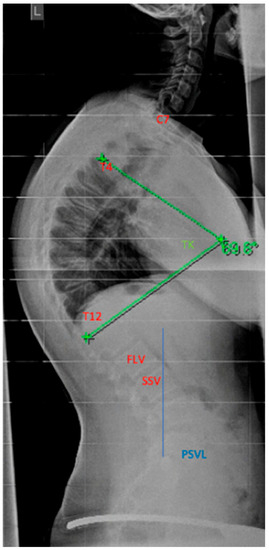

4.2. Diagnostics

Although initially described by Sorensen, the definition of SD has been definitively established by subsequent work by Edgren et al. and Blumenthal et al., with SD typically manifesting mostly in the thoracic spine (type I) and less commonly in the lumbar spine (type II) [79,85,86]; see Figure 7. The measurement of thoracic kyphosis according to Cobb (Th1–Th12) is sometimes difficult on conventional X-rays due to the humeral heads, so the Stagnara angle (Th4–Th12) is a reliable alternative (Figure 8). In children with SD, back pain and a positive family history are common, and clinical examination typically reveals a gibbus and a flexible deformity. In addition to a detailed medical history, a thorough physical examination is of utmost importance. The various signs and findings typical of SD are listed in Table 2.

4.4.1. Selection of the Instrumentation Range

The determination of the instrumentation range is certainly dependent on the chosen surgical procedure. The upper instrumented vertebra (UIV) is usually the proximal vertebra that still belongs to the curvature [104]. The selection of the lowest instrumented vertebra (LIV) can be the first lordotic vertebra (FLV) or the sagittal stable vertebra (SSV) according to Cho et al. [105]; see Figure 12. However, in the meta-analysis by Gong et al., instrumentation of the SSV proved to be superior to the FLV [106]. In this meta-analysis, the incidence of distal junctional kyphosis (DJK) in SD was reported to be 20.8%, and of these cases, 27.8% of patients had to be revised; 5.9% of the SSV cohort and 43.6% of the FLV cohort developed DJK [106].

Figure 1. Examples for determination of growth potential according to Sanders of ne non-dominant left (L) hand [21]. (ac) and Risser [22] (df), (a)—Sanders 2, (b)—Sanders 3, (c)—Sanders 5, (d)—Risser 0, (e)—Risser 2, (f)—Risser IV.